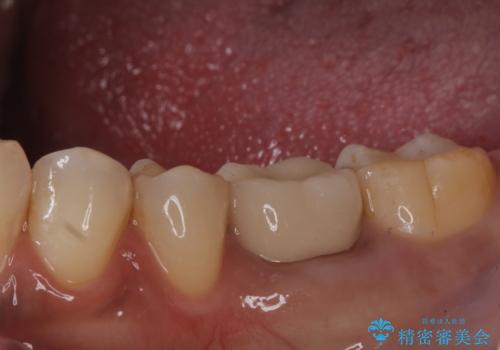

銀歯がとれた セラミックインレーで修復

拡大鏡下で丁寧に虫歯を取り除き、セラミックインレーによる修復治療を行いました。

今回は銀歯が取れたので、虫歯が神経まで達して痛みが出る前に、強度・審美に優れ、虫歯の再発の少ないセラミックインレーにて治療を行うことができました。